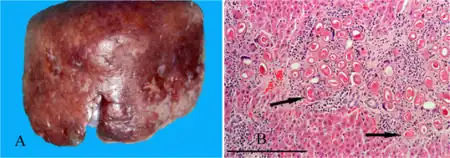

a,b)Hepatic capillariasis | |

- Hepatic capillariasis, caused by Capillaria hepatica